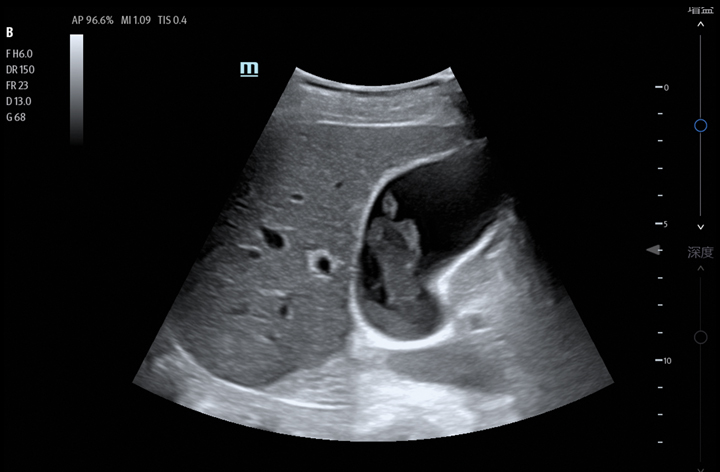

The TE7 Max Ultrasound System is designed to maximize your capabilities in demanding Point of Care environments. With its thoughtful industrial design and best-in-class image quality, the

TE7 Max provides a superior user experience during rapid clinical assessments and procedures taking place at the patient’s bedside

The TE7 Max boasts a large 21.5” vertically oriented high-definition display and a sealed touch-based interface to optimize visualization and accessibility when every second counts. The TE7 Max also incorporates a comprehensive suite of artificial intelligence (AI) powered Smart Tools and workflow enhancement software (iWorks™ Protocol) making efficiency and reproducibility the expectation for all end users.